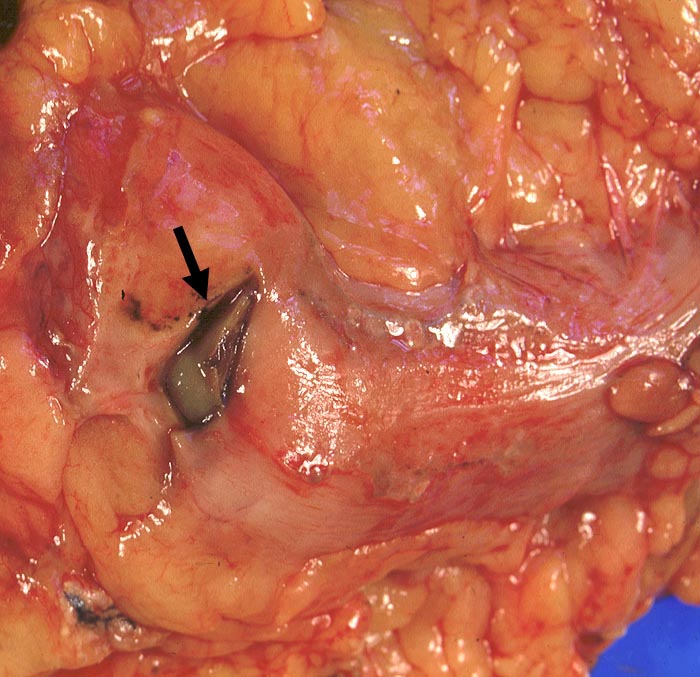

Magenulkus : freie Perforation

Blick auf den uneröffneten Magen. Grosse Perforationsstelle. Nur geringe Peritonitis (matter Serosaüberzug).

Sekundärer Morbus Cushing bei Steroidtherapie von COPD. Alkoholabusus.